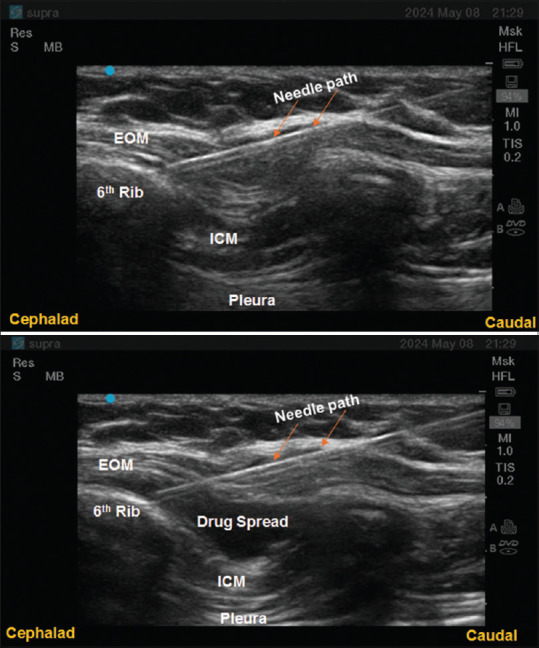

External oblique intercostal plane block in paediatric patients with thrombocytopenia for open splenectomy: Simple and promising….